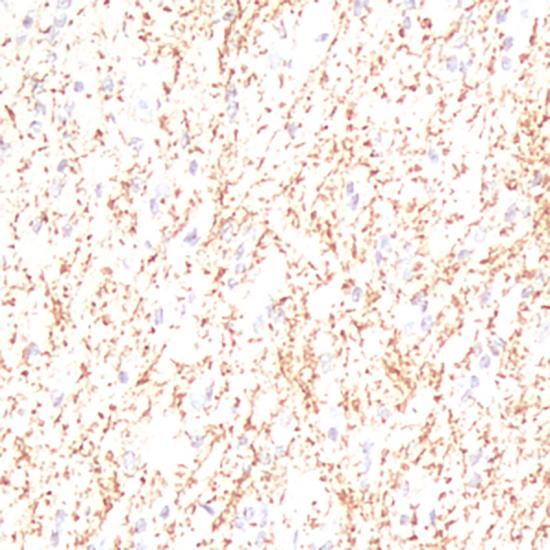

IDH-1R132H突變見(jiàn)于星形細(xì)胞瘤、少突膠質(zhì)細(xì)胞瘤和少突星形細(xì)胞瘤以及繼發(fā)性膠質(zhì)母細(xì)胞瘤,且預(yù)后明顯好于野生型。因此,對(duì)于IDH1基因突變的確定是膠質(zhì)瘤病理學(xué)診斷和預(yù)后評(píng)估的重要參考指標(biāo)。克隆號(hào)為H09的IDH1單克隆抗體可特異性的檢測(cè)腦組織腫瘤中IDH1基因的R132H點(diǎn)突變。

IDH-1抗體試劑(免疫組織化學(xué)) 閩廈械備20180103號(hào)

• 陽(yáng)性部位:

細(xì)胞漿

• 陽(yáng)性對(duì)照:

星形細(xì)胞瘤